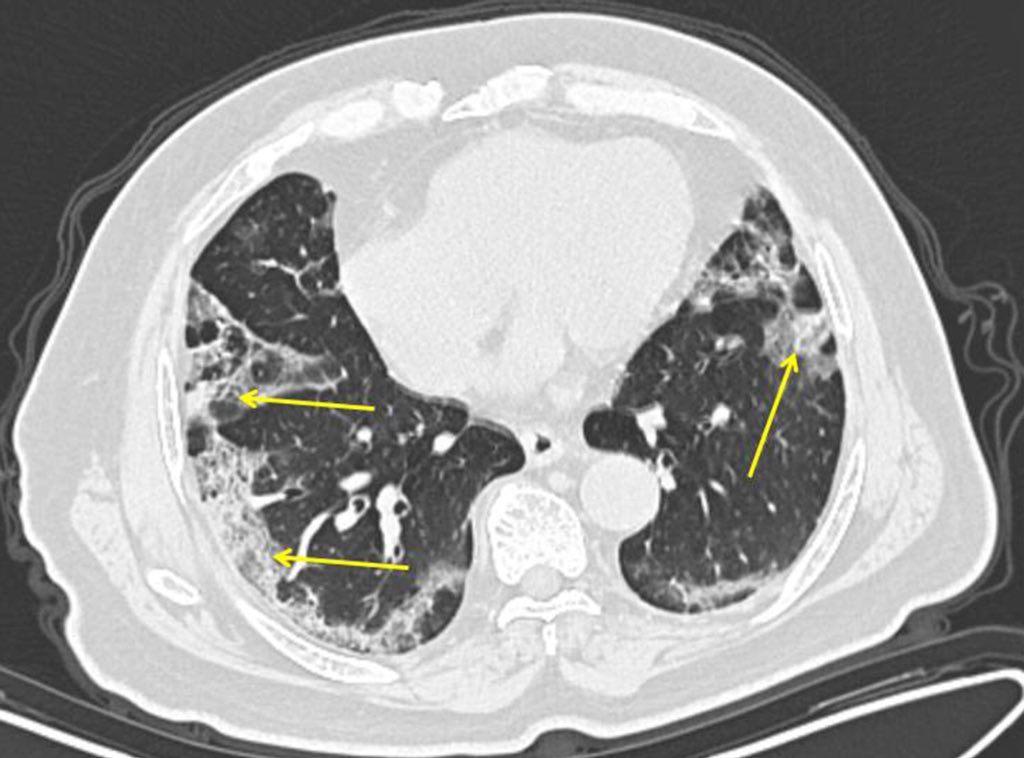

لكن البعض الآخر يتدهور ، غالبًا بشكل مفاجئ تمامًا ، ويطور حالة تسمى متلازمة الضائقة التنفسية الحادة (ARDS). حيث تنخفض مستويات الأكسجين في دمائهم ويجدون صعوبة أكبر في التنفس.

(20)

في صور الأشعة السينية والاشعة المقطعية، تظهر الرئتان مليئتان بالعتامة البيضاء حيث يجب أن تكون المساحة السوداء (الهواء). (21)

عادة ما يحتاج هؤلاء المرضى الى ان يوضعوا على أجهزة التنفس الصناعي ... وقد يموت 50% منهم تقريباً ... وتظهر عمليات التشريح أن الحويصلات الهوائية أصبحت محشوة بالسوائل وخلايا الدم البيضاء والمخاط وبقايا خلايا الرئة المدمرة. (22)